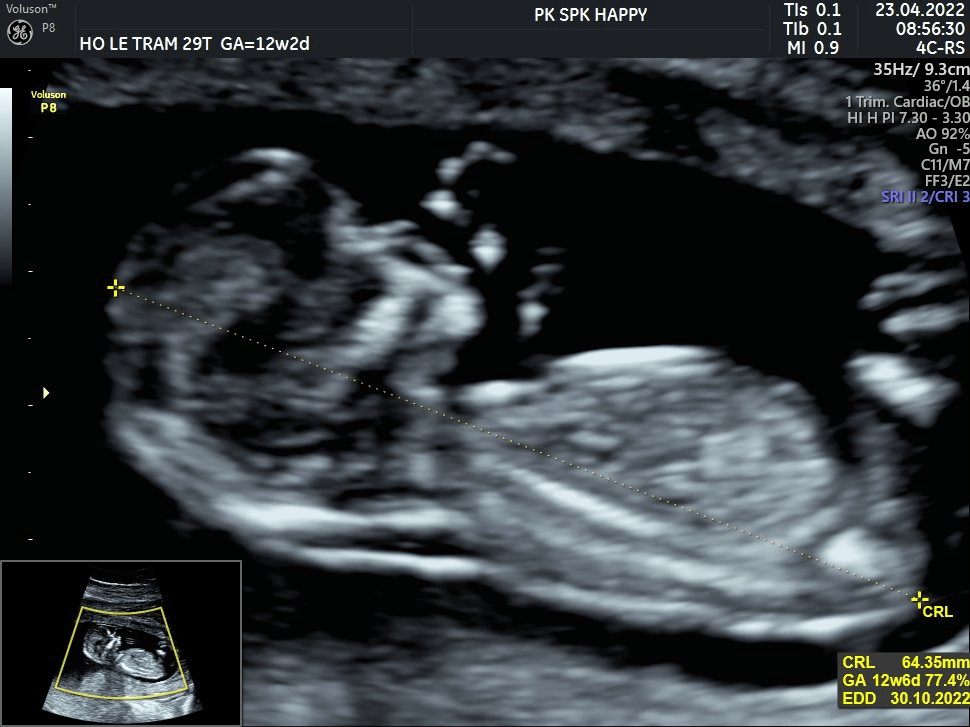

25/04: tuần trước hai bố mẹ đưa mỡ đi khám mốc 12 weeks ; trộm vía Mỡ phát triển nhanh và khỏe mạnh. Mẹ cứ rảnh rảnh là lại tưởng tượng đến khoảnh khắc múa may quay cuồng, ưỡn ẹo lộn nhào của em, đang ngủ say sưa bị bác sĩ đập dậy nên ưỡn ẹo rồi lại ngủ tiếp. chờ mãi chờ mãi em mới dậy tiếp để bác sĩ đo độ mờ da gáy thì em xoay mù trời, lộn vòng. Dễ thương hết sức luôn; Mấy hôm nay mẹ cứ ngắm ảnh mỡ suốt cả ngày luôn được; nhìn tay, chân rồi đoán già đoán non xem mỡ giống ai. Có mỡ thật là một điều kỳ diệu :D.

28/04/2022: chin chào Mỡ đến với chuyên mục lảm nhảm buổi sáng của mẹ. Sáng nay cũng xử xong được hai việc rồi nên thảnh thơi xíu, cuối tuần này mẹ sẽ đưa mỡ đi bơi ở nhà o Ly con nha. Một bức ảnh đầu tiên lúc em 12 weeks nè. Mong chờ được đón chào em đến với thế giới quá. Thời gian này cứ tận hưởng trong bụng mẹ nha Mỡ.